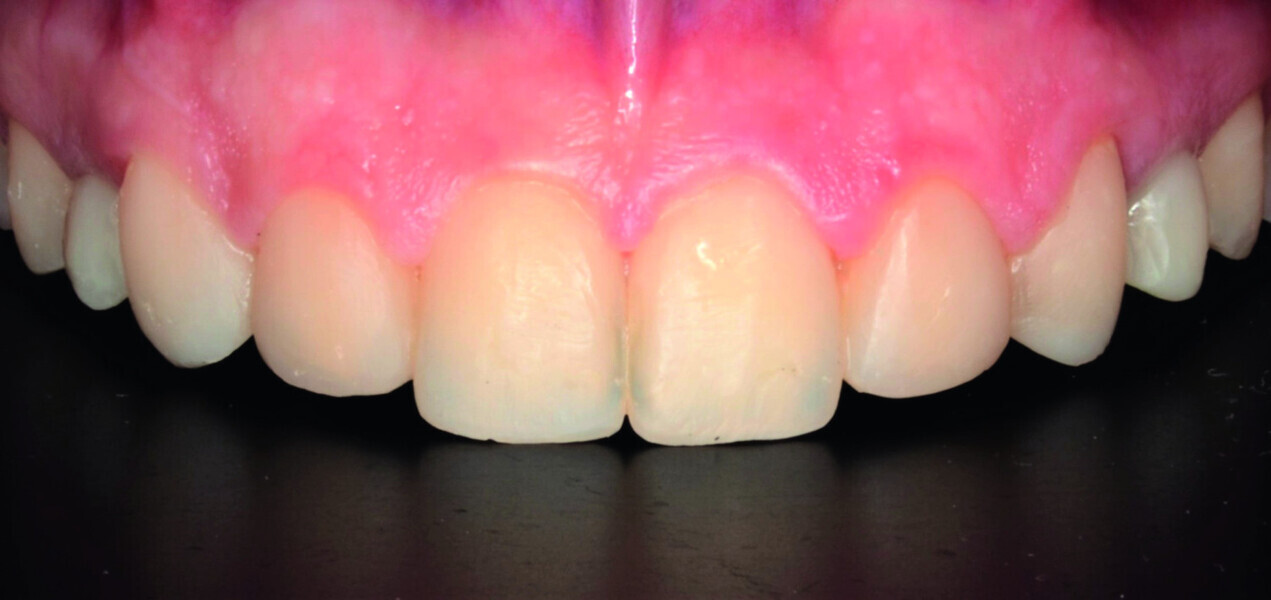

Orthodontic management of maxillary lateral incisors agenesis